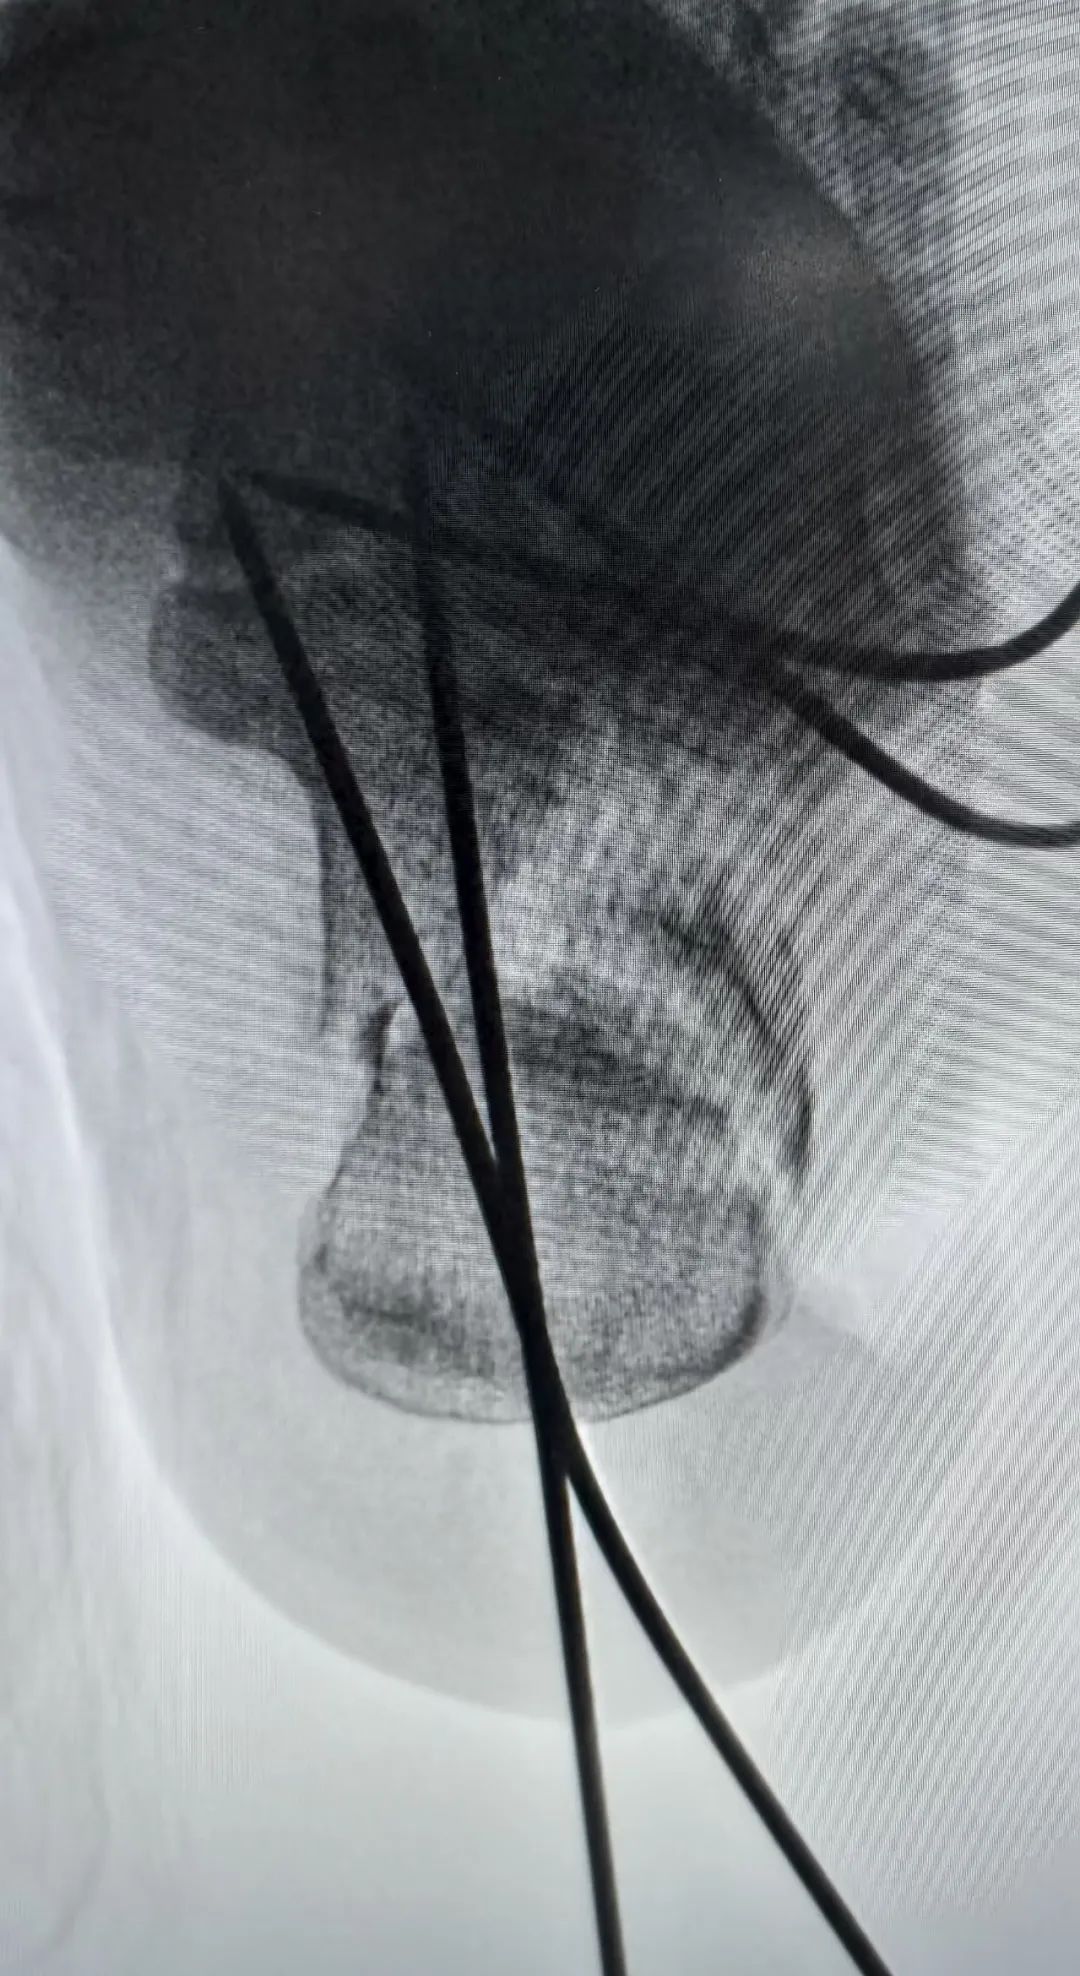

术中采取打开内侧壁后结合术中骨刀撑开合并上述手法复位内翻,然后给予克氏针固定与稳定的载距突,达到矫正并稳定内翻复位。(很多人复位位置很好,但总是固定不住,最主要的原因就是没有固定骨折块于稳定的骨折块上,固定于载距突可以很好的解决这个问题)

解决内翻之后,复位关节面,同时复位G角和舌型骨折块,辅助克氏针临时固定,可以很好的固定骨折。术中可以看到解剖复位。

这一例也是采用同样的方法,复位内翻之后,克氏针临时固定,钛针固定载距突方向复位关节面。最终解剖复位。

个人认为先复位内翻畸形,再复位关节面更有利于操作,同时无论是内翻纠正还是关节面的复位,载距突都是非常重要的复位标志及固定选择。